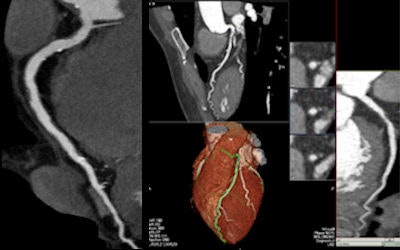

![]() |

| In a 49-year-old woman with exertional chest pressure and a family history of coronary artery disease, prospectively gated 320-slice CT angiography ruled out coronary artery disease with a radiation dose of 2.1 mSv. All images except one noted below are courtesy of Dr. Tony DeFrance. |